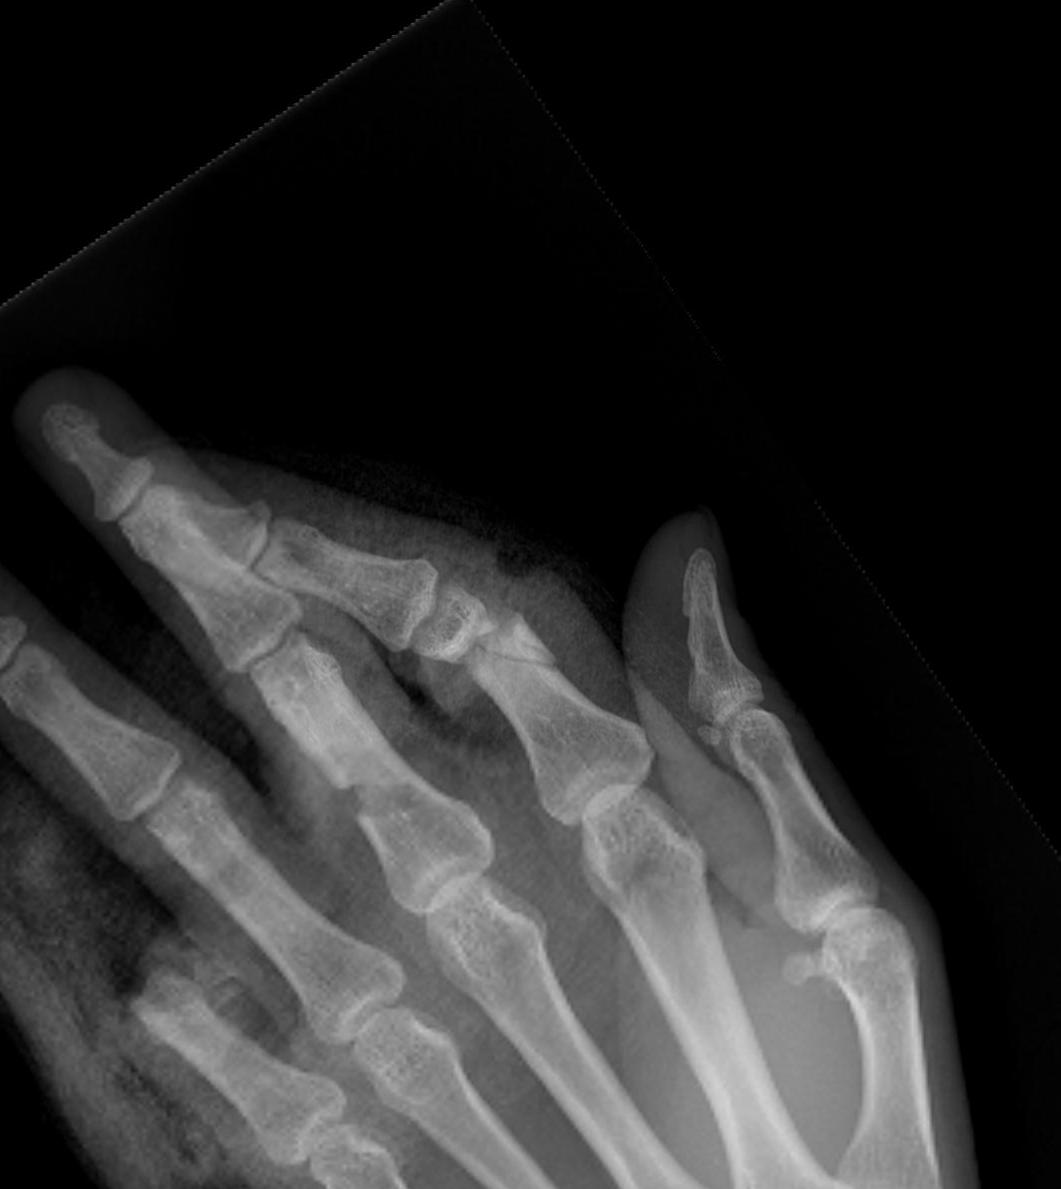

X-rays

3 planes centred on MCPJ middle finger

- AP

- lateral

- oblique

Care to look for subtle evidence joint subluxation